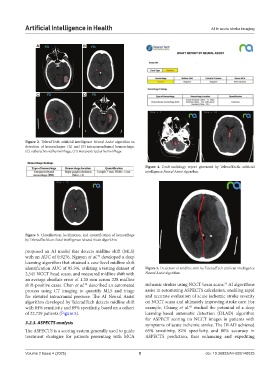

Figure 2. TeleradTech artificial intelligence Neural Assist algorithm in

detection of hemorrhages: (A) and (B) intraparenchymal hemorrhage,

(C) subarachnoid hemorrhage, (D) intraventricular hemorrhage

Figure 3. Classification, localization, and quantification of hemorrhage

by TeleradTech’s artificial intelligence Neural Assist algorithm